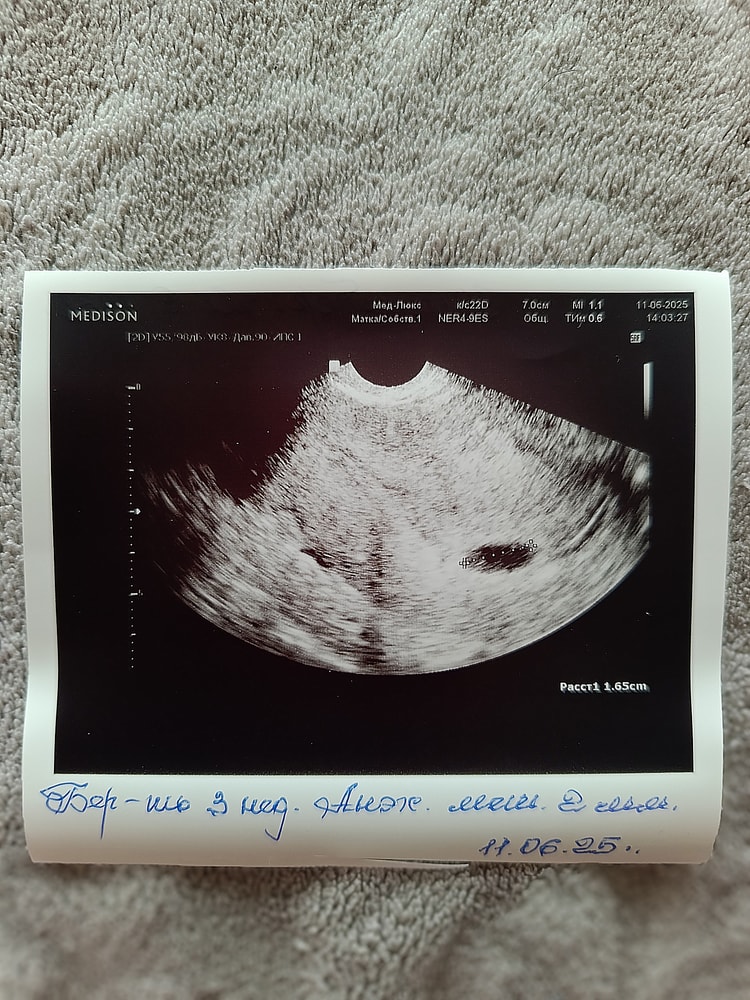

Сегодня сходила на УЗИ. Маточную беременность подтвердили😊

Вера , желточный мешочек 2 мм соответствует 3м эмбриональным неделям.

Эмбриона не видно.

Через неделю будет видно)